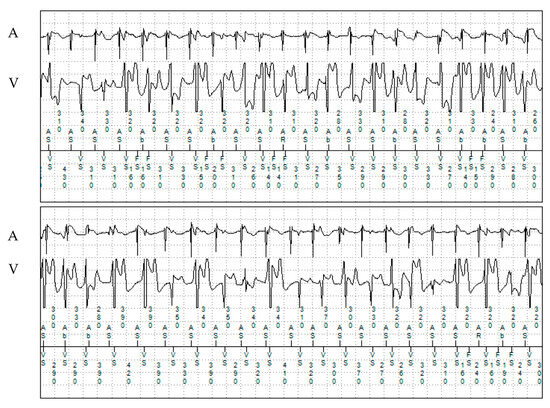

Genetic screening (Sanger sequencing) showed a RYR2 variant of uncertain significance (VUS) (c.11954 T>A; p.Met3985Lys). Genetic screening of both of the patient’s parents and his sister were negative, suggesting a de novo variant or a different father in the index patient. The patient had additional paroxysmal atrial fibrillation (AF) and atrial flutter (partially with 2:1 conduction), which started at the age of 18. The longest detected episode of an atrial tachyarrhythmia during remote monitoring was 1 h 21 min. (Figure 1 and Figure 2). The patient remained asymptomatic for these atrial arrhythmias. No oral anticoagulation was prescribed as he had a CHA2DS2-VASc score of 0.

Figure 1. Ventricular and later sustained arrhythmia episodes in patient 1 documented on his dual-chamber ICD with remote monitoring. A: atrial electrogram; V: ventricular electrogram.

Figure 2. Monitored episode of atrial fibrillation in patient 1. A: atrial electrogram; V: ventricular electrogram.